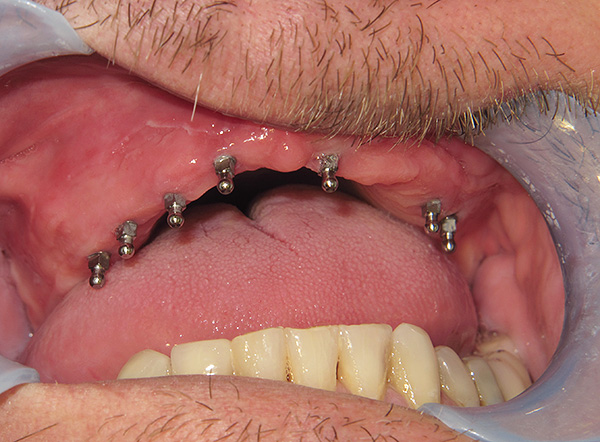

Le fotografie seguenti mostrano un esempio di impianto di un dente anteriore appena rimosso (che si è rotto da una lesione meccanica):

nota

In alcune situazioni, quando le condizioni del tessuto osseo lo consentono e l'impianto ha una fissazione primaria abbastanza buona, è possibile installare una corona in metallo-plastica economica per il periodo di osteointegrazione dell'impianto. Per i denti anteriori, questo è particolarmente importante, poiché consente di ripristinare l'estetica della dentatura in modalità express. Considerando che i denti anteriori non sono coinvolti nella masticazione del cibo, il carico sull'impianto sarà minimo.